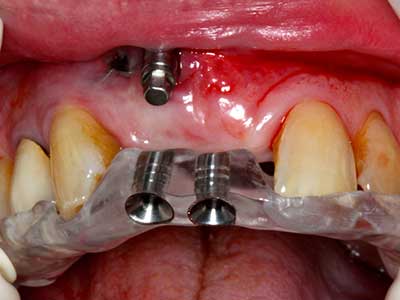

Fig. 13: l'irrigazione adeguata con l'osso residuo largo 4 mm è essenziale durante l'incisione ossea di questo paziente di 52 anni.

Fig. 14: posizionamento di quattro impianti RSX conici (BEGO Implant Systems, Brema).